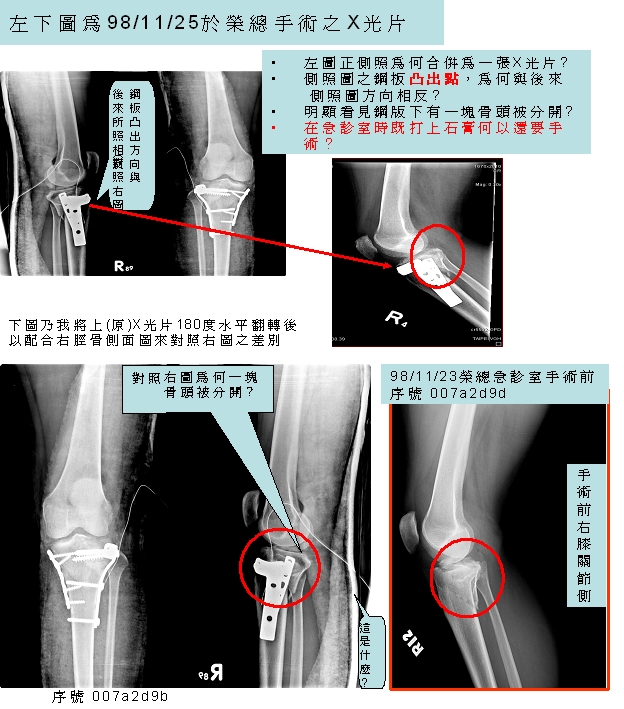

民眾提供之骨科糾紛案例01